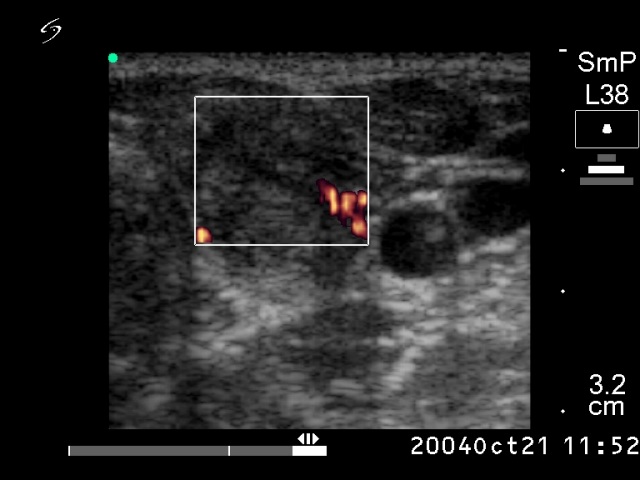

Ethanol sclerotherapy: non-toxic solid nodules - Case 5

Six month after the therapy (ultrasonographic picture 2)

Left lobe, horizontal scan, power Doppler mode. The nodule presents intranodular blood flow.